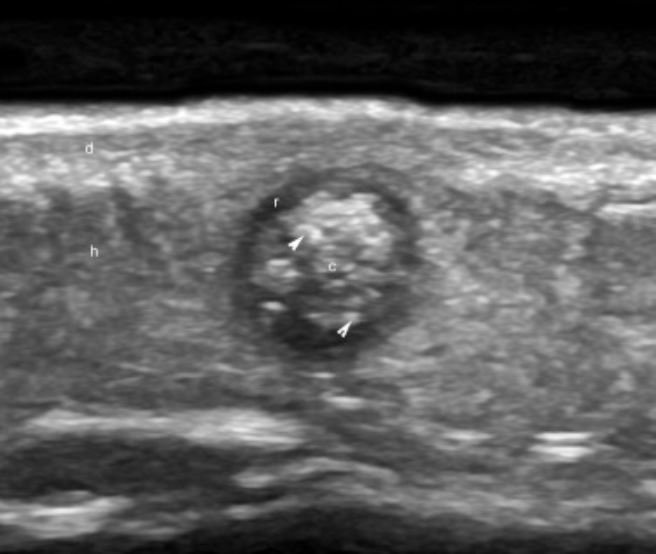

3. Hình ảnh U thượng bì vôi hóa (pilomatrixoma) trên siêu âm

Khối hỗn hợp hình bầu dục, thường có vôi hóa đi kèm, tại vị trí nối giữa chân bì và lớp mỡ dưới da có một lớp da mỏng phủ lên.

Xuất hiện như dấu hiệu hình bia bắn với vùng giảm âm kết nối với bao mô và tăng âm ở trung tâm của vùng tế bào biểu mô.